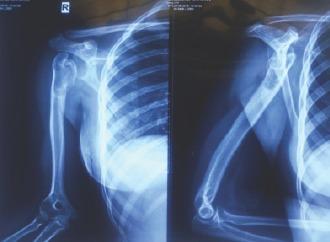

We report a case of a 17-year-old girl with physeal arrest at the proximal physis of the humerus with etiology of post-trauma/post-infection. She presented with a shortening of 8 cm and restricted shoulder movements. We performed a lengthening of the humerus based on the principle of distraction osteogenesis. We used the paediatric limb reconstruction system to distract the corticotomy. However, postoperatively, she developed radial nerve palsy, despite our intraoperative precautionary measures. Distraction was started at 1mm/day. She then showed the progress of radial nerve recovery and full recovery was noted by 5 months post-operatively. The length of the distraction compression assembly had to be changed twice to longer sizes to accommodate the required amount of lengthening. After consolidation of regenerate was confirmed with serial radiographs, external fixator was removed. She was then maintained on a functional brace. We were able to achieve 8cm of lengthening following distraction, and the cosmetic appearance of the patient improved to the patient's and attenders' satisfaction.

我们报告一例17岁女孩,肱骨近端骨骺因创伤后/感染后病因出现骨骺阻滞。她表现为缩短8厘米且肩部活动受限。我们基于牵张成骨原理进行了肱骨延长术。我们使用儿童肢体重建系统对截骨部位进行牵张。然而,术后她出现了桡神经麻痹,尽管我们术中采取了预防措施。牵张从每天1毫米开始。然后她显示出桡神经恢复的进展,术后5个月实现了完全恢复。牵张加压装置的长度不得不两次更换为更长尺寸以适应所需的延长量。经系列X线片确认再生骨愈合后,拆除了外固定架。然后她佩戴功能性支具。牵张后我们成功实现了8厘米的延长,患者的外观改善,患者及其家属表示满意。